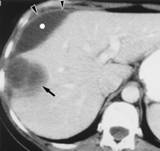

Loại tổn thương thứ 2 đặc hiệu hơn, loại tổn thương có hình ảnh giảm âm (hypodense), với các đường ngoằn nghoèo như hình con rắn trên phim chụp CT. Sự xuất hiện trên CT các hình ảnh bao gan dày và nhu mô gan giảm nhiều cũng được mô tả như thể hình ảnh CT của bệnh sán lá gan lớn đặc trưng. Một hình ảnh tụ máu dưới bao gan lớn đơn thuần sẽ không đặc trưng cho bệnh sán lá gan lớn. Một hình ảnh tụ máu dưới bao gan có xuất huyết có thể là một biến chứng trong giai đoạn sán xâm nhập. Trong trường hợp hiếm, chảy máu có thể đe dọa tính mạng bệnh nhân vì độ trầm trọng và khả năng chảy máu tái phát. Sự liên quan của u máu dưới bao gan kèm theo tăng bạch cầu ái toan tăng cao sẽ đề nghịhoặc là viêm đa động mạch nút (polyarteritis nodosa) hoặc sán lá gan giai đoạn xâm nhập. Trong giới hạn với sự hiểu biết của nhóm nghiên cứu, một tổn thương dưới bao gangây ra bởi sán lá gan lớn gây abces dường như hiếm khi được báo cáo trong y văn.

Thông thường một bệnh nhân có khối máu tụ dưới bao gan như thế sẽ có cơn đau cấp tính và trên CT sẽ cho hình ảnh giảm âm giúp cho chẩn đoán. Tuy nhiên, CT của một khối máu tụ không phải cấp tínhlà một trường hợp tương tự như viêm: cả hình ảnh giảm âm dưới bao gan. Mặt khác, không thấy dấu hiệu thiếu máu và bao gan dày lên giảm đậm độ xung quanh có thể giúp xác định loại trừ nguyên nhân khác. Nếu vẫn còn nghi ngờ, cần thiết phải chọc dò kim nhỏ để giúp chẩn đoán xác định tốt hơn.  | Hình ảnh trên CT cho thấy các đường vòng, vết xoắn vặn (đặc điểm của sán lá gan lớn) và chùm tổn thương dạng nốt nhỏ, kể cả vị trí dưới bao gan và khi đó bao gan vẫn còn nhìn thấy. |